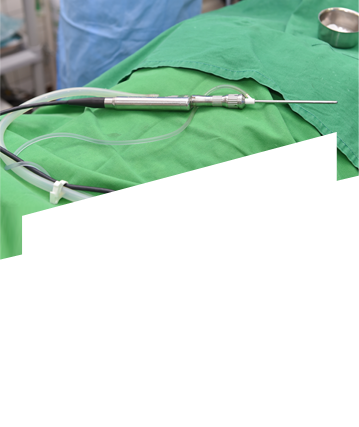

축농증 수술 네비게이션 장비 강남점 도입!

“실시간 교통상황보다 정확한 실시간 콧속상황”

네비게이션 축농증 수술 동영상으로 직접 확인해보세요

수술 도구 삽입